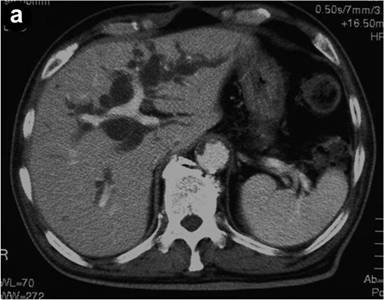

A 72-year-old man was admitted to our hospital with jaundice. He had a 15-year history of diabetes mellitus. There were no palpable masses or lymph nodes at physical examination. Full blood count and renal values were normal, but liver biochemistry showed total bilirubin of 11.7 mg/dL (reference range: 0.2-1.0 mg/dL), direct bilirubin of 8.8 mg/dL (reference range: 0.1-0.4 mg/dL), AST of 88 IU/L (reference range: 0-40 IU/L), ALT of 184 IU/L (reference range: 0-40 IU/L), alkaline phosphatase of 3,414 IU/L (reference range: 115-360 IU/L) and GGT of 1,356 IU/L (reference range: 10-60 IU/L). The serum level of CA 19-9 was elevated to 69 U/mL (reference range: 0-37 U/mL), that of DUPAN-2 was 1,320 U/mL (reference range: 0-150 U/mL) and that of SPAN-1 was 63 U/mL (reference range: 0-150 U/mL). Computed tomography showed dilatation of both the biliary tract and the main pancreatic ducts as well as an enhanced mass lesion measuring 1.5 cm in the pancreatic head (Figure 1). These findings suggested the existence of a tumor involving the ampulla of Vater. Endoscopic examination showed a reddish swollen papilla of Vater (Figure 2). Pathological findings on biopsy from the papilla suggested tubular adenocarcinoma and signet-ring cell carcinoma. Endoscopic examination of the stomach and the colon did not disclose any other foci of signet-ring cell carcinoma. Having diagnosed carcinoma of the ampulla of Vater, a pancreaticoduodenectomy was performed.

Figure 1. Abdominal axial computed tomography images. a. Computed tomography showed dilatation of the intrahepatic biliary tract. b. An enhanced mass lesion measuring 1.5 cm was detected in the pancreatic head. |